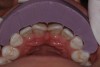

Fig 19. Preoperative lingual view before scaling and root planing.

Figure 19